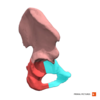

Structure: Ilium

structure: iliac crest

structure: tubercle of iliac crest

structure: anterior superior iliac spine (asis)

structure: anterior inferior iliac spine

structure: Posterior superior iliac spine

structure: posterior inferior iliac spine

structure: iliac fossa

strucure: anterior gluteal line

structure: acetabulum (specifically this is the lunate this implies the entire acetabulum)

structure: acetabular notch

structure: acetabular fossa

structure: ischial tuberosity

structure: greater sciatic notch

structure: lesser sciatic notch

Structure: pubis

structure: body of pubis

structure: pubic tubercle

Structure: Superior Ramus of pubis

Structure: Inferior Ramus of pubis